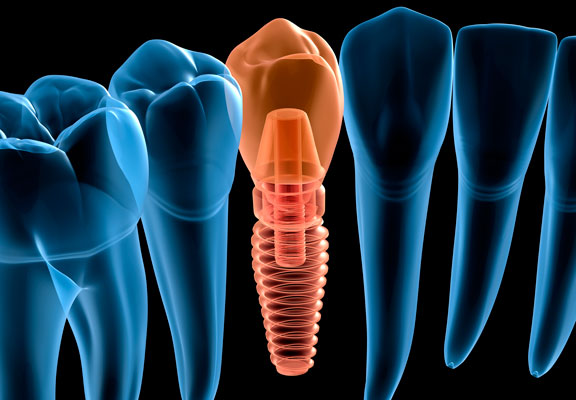

5. Nuestro cuerpo puede rechazar un implante

VERDAD

MITO

¡Incorrecto! Realmente no es el cuerpo el que rechaza un implante, porque estos se fabrican con materiales biocompatibles. Lo que se conoce comúnmente como “rechazo” son problemas generados en el proceso de osteointegración, normalmente vinculados con una higiene dental deficiente, que provoca que la encía no cicatrice adecuadamente tras la colocación del implante.

¡Correcto! El cuerpo no puede rechazar un implante porque se fabrican con materiales biocompatibles. Las complicaciones que pueden aparecer derivan del proceso de osteointegración y solo aparecen en el 2% de los pacientes que se someten a este tratamiento.